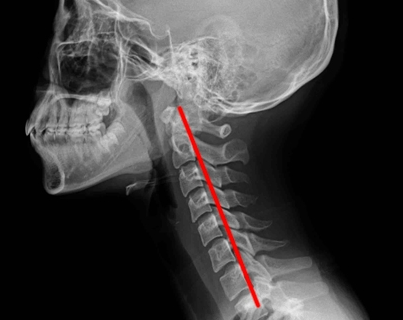

일자목통증은 현대인들에게 매우 흔한 증상 중 하나입니다. 컴퓨터와 스마트폰의 사용이 증가하면서 목에 부담이 가해지고, 이로 인해 일자목통증이 발생하는 경우가 많아졌습니다. 하지만 걱정하지 마세요! 이 글에서는 일자목통증의 원인과 예방법, 그리고 치료법에 대해 자세히 알아보겠습니다.

일자목통증의 원인은 다양합니다. 가장 대표적인 원인은 잘못된 자세입니다. 컴퓨터나 스마트폰을 사용할 때 목을 앞으로 내밀거나 억지로 자세를 유지하는 경우, 목과 어깨 근육이 긴장되어 일자목통증이 발생할 수 있습니다. 또한, 교통사고나 낙상 등의 외상으로 인해 일자목통증이 발생할 수도 있습니다.